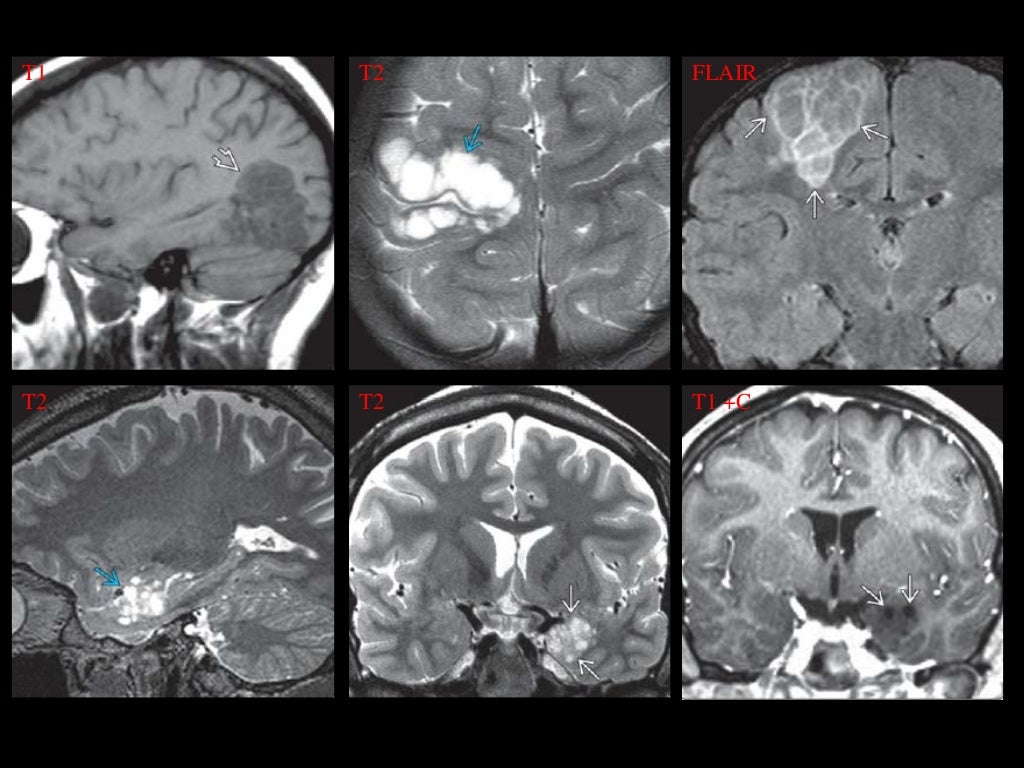

La imagen por resonancia magnética (MRI, MRI) o tomografía computarizada (TC) muestra lesiones en la corteza cerebral. Las lesiones se extienden en todo el espesor de la corteza. En la TC se puede ver densas lesiones de la corteza con discapacidad (hipodensa) bien delimitadas . Los quistes se encuentran a menudo calcificados. Una acumulación de medio de contraste no es típica. Un desplazamiento del tejido circundante no se produce. A veces hay una deformidad del cráneo sobre el tumor. En la RM, las lesiones aparecen bien definidas, no invasoras, y sin edema perifocal (captación de líquido en el parénquima cerebral circundante). Como es típico, la configuración multinodular (que consta de muchos como estructuras nodulares) se ha descrito.[1][7]